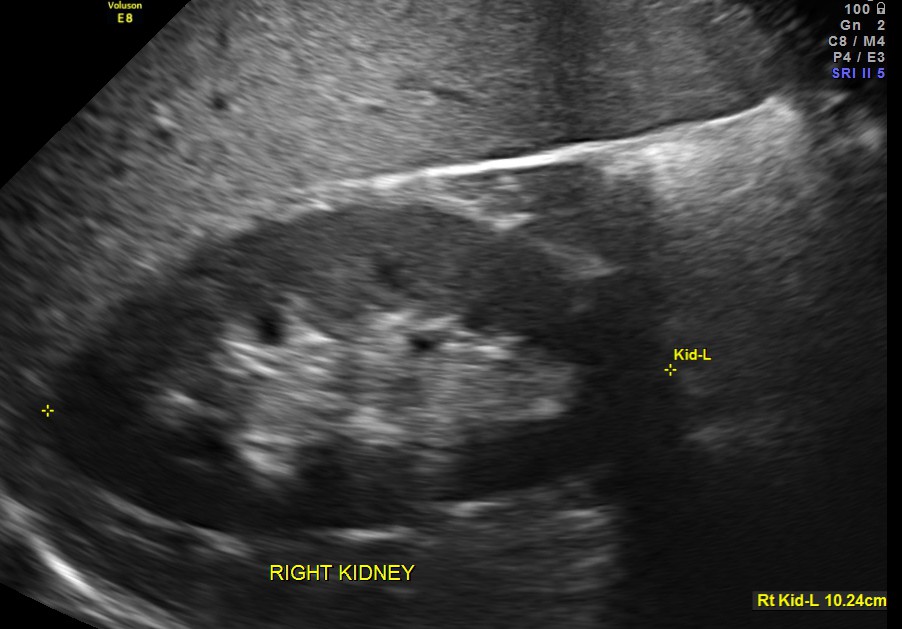

The following pictures were obtained.

The scan was otherwise normal.